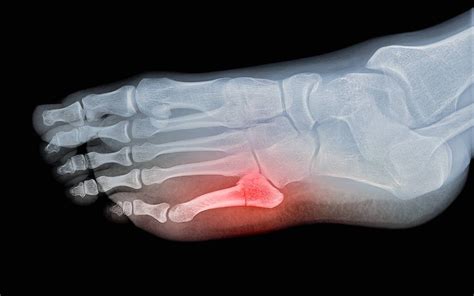

An ankle injury can range from a mild sprain to a debilitating fracture, and distinguishing between the two is crucial for proper recovery. Understanding the broken ankle signs and symptoms is the first step in determining whether you need to seek immediate medical intervention or if the injury can be managed with conservative home care. Because the ankle is a complex joint composed of three bones—the tibia, fibula, and talus—a break can occur in various locations, leading to a wide array of symptoms that often mimic less severe injuries. Recognizing these signals early can prevent long-term complications and ensure that you get the right treatment plan tailored to your specific injury.

Anatomy of an ankle showing the tibia, fibula, and talus bones

Once you arrive at a clinic, the medical team will assess the broken ankle signs and symptoms through a physical examination and imaging. The doctor will gently palpate the bony prominences of your ankle to identify where the tenderness is most acute. Following this, they will order diagnostic imaging. X-rays remain the gold standard for identifying fractures, as they provide a clear view of the bone structure. In more complex cases, such as those involving the joint surface or hairline fractures that don’t appear on standard X-rays, a CT scan or MRI may be requested to obtain a more detailed cross-sectional view of the damage.